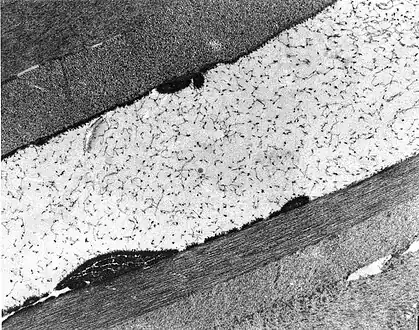

Congenital stromal dystrophy. Transmission electron microscopy of the corneal stroma showing normal collagen lamellae separated by abnormal randomly distributed collagen filaments in an electron-lucent extracellular matrix.